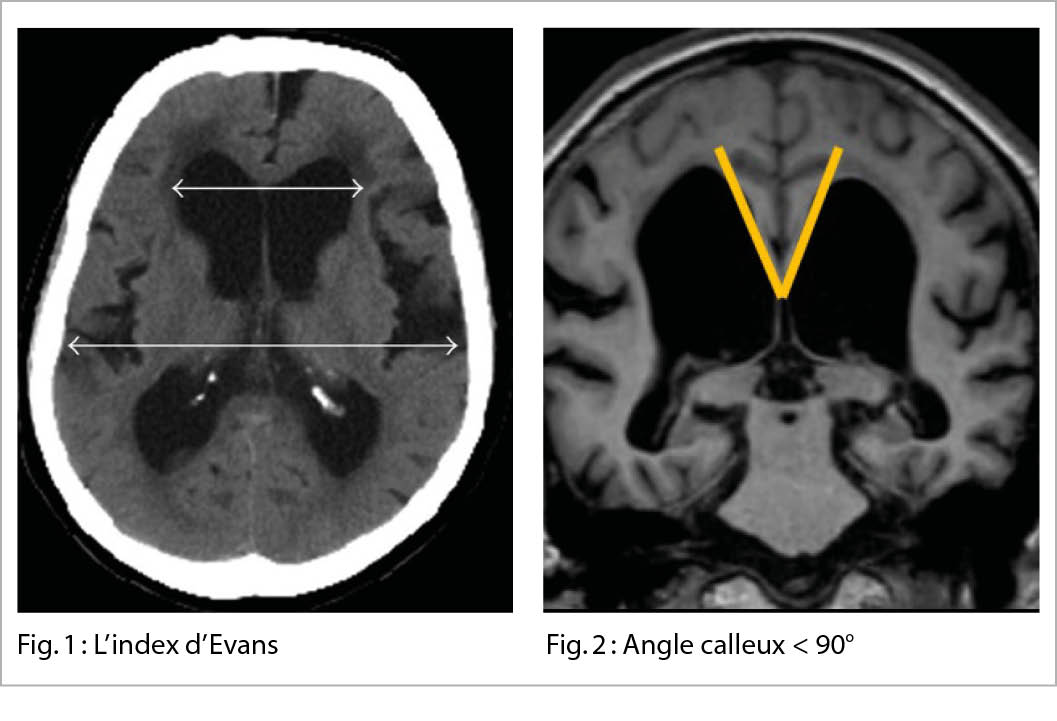

• L’ index d’ Evans (figure 1), mesure la largeur des deux cornes frontales rapportée au diamètre endocrânien correspondant sur une coupe axiale. Lorsque ce dernier est supérieur à 0.3, les ventricules sont considérés comme élargis, indépendamment de la pathologie sous-jacente.

• L’ angle calleux (figure 2) inférieur à 90°.